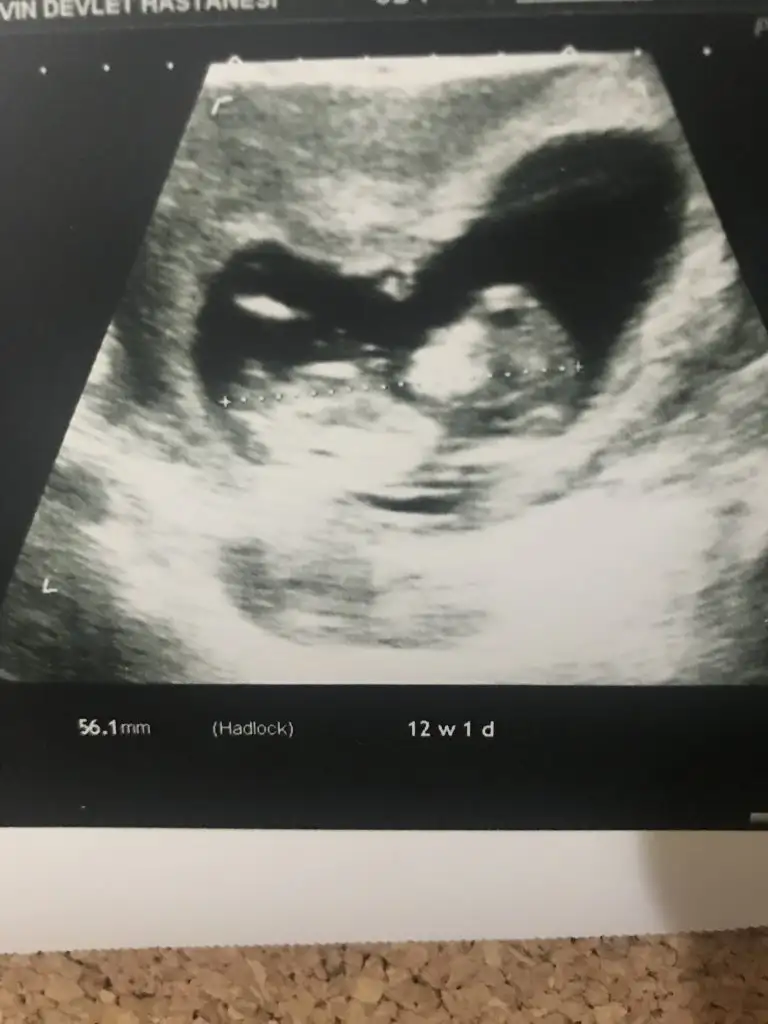

Slm güzel anneler bizde 11+1haftalik olduk bizede bir tahmin edermisiniz

Net degil gördüğüm diklik nub ise erkek gibi ama eminde değilim başka usg varmı 11 yada 12 hafta